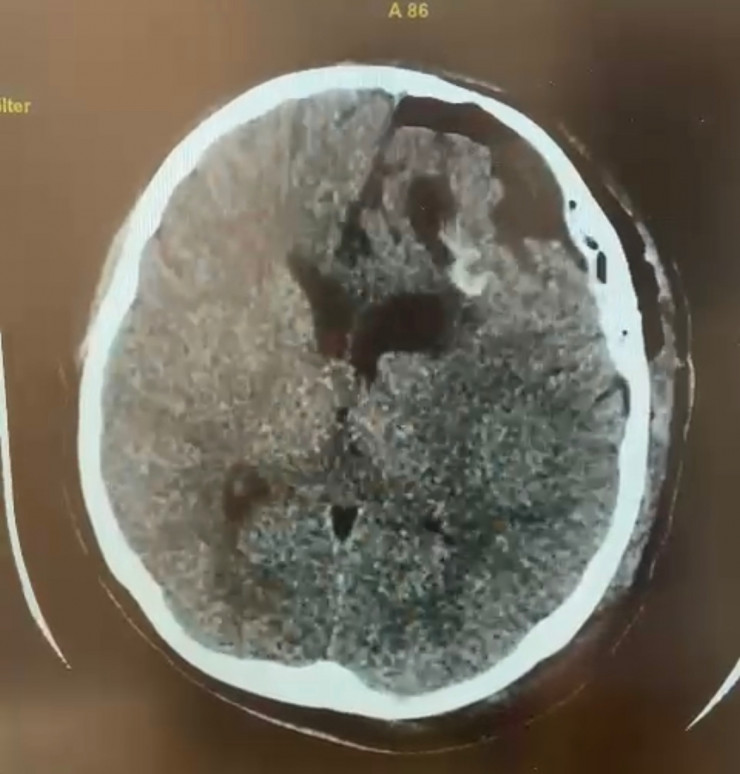

За короткое время был установлен диагноз "эхинококкоз" и принято решение о трепанации черепа и извлечении опухоли. Незамедлительно она была прооперирована.

КТ-снимок после операции. Материал предоставлен общественным объединением KAZNEURO